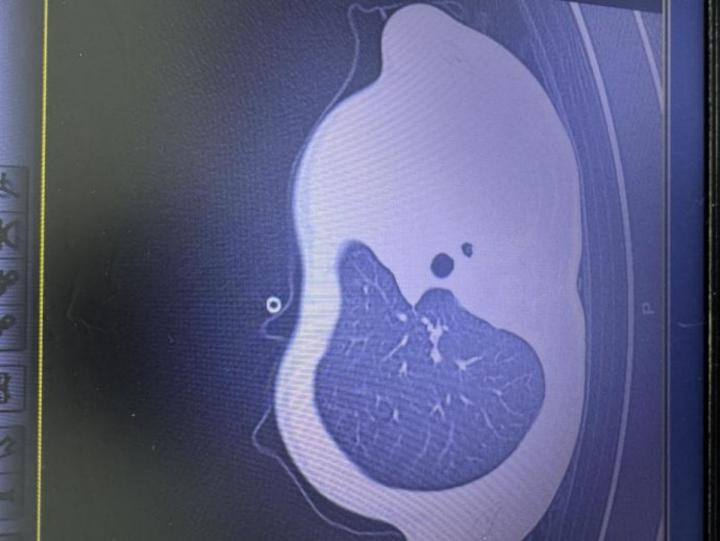

急诊查验摈弃让医护东说念主员一忽儿急切:验血败露炎症筹算大幅飞腾,胸片更发现左侧肺叶简直“不职责了,影像学中酿成大片白色,即常常所说的“白肺”,意味着肺功能严重受损,孩子仍是缺氧,随时有窒息危机。

图:影像败露肺白了一半

“这是流感销毁细菌感染引起的严重肺炎,同期发生了坏死性喉气管支气管炎,一种严重并发症:黏稠痰栓会像树枝一样堵在气说念分支处,导致肺部无法平常通气,若不足时贬责,几小时就可能防止生命!”杨子浩主任医师回忆。